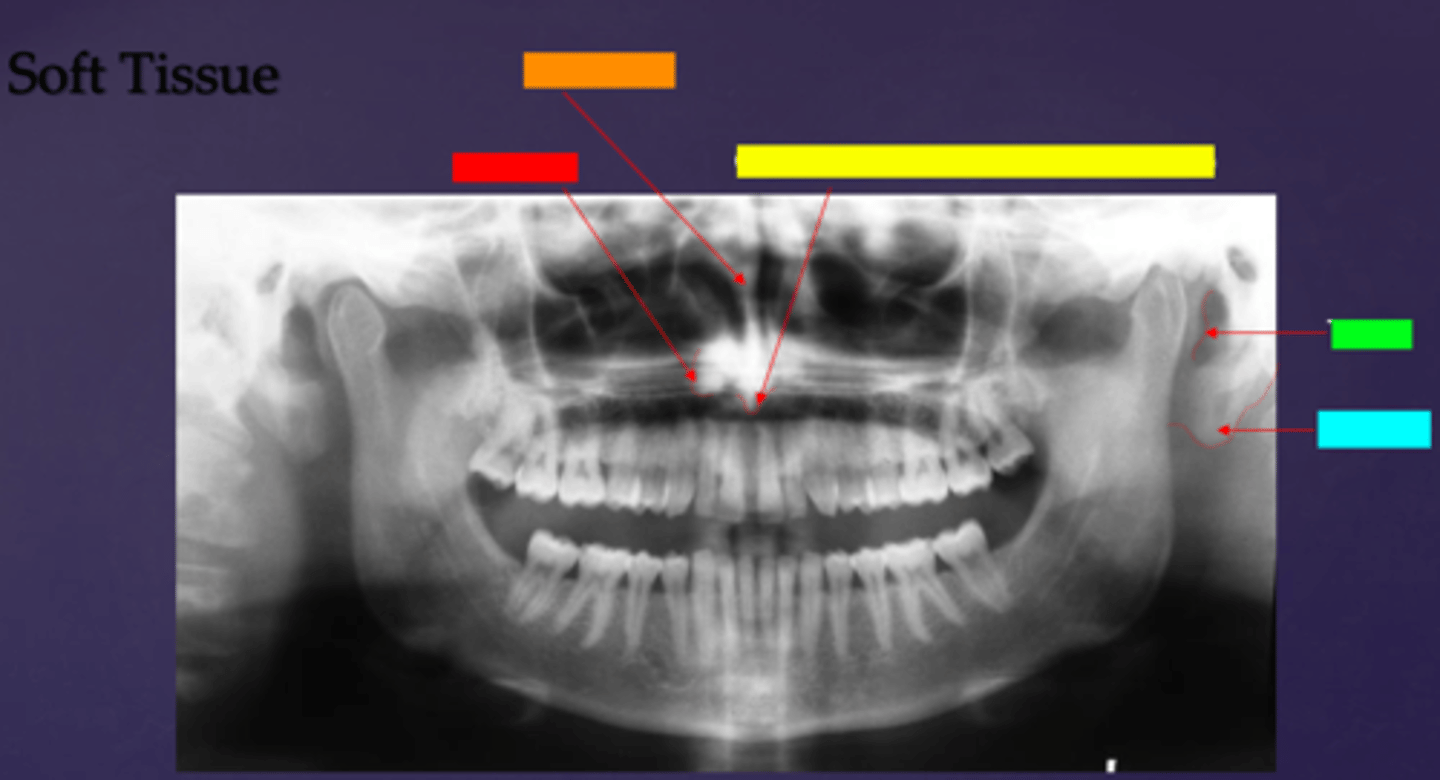

ID the soft tissue anatomy indicated by the arrow pointing from the red box:

ala of nose

ID the soft tissue anatomy indicated by the arrow pointing from the orange box:

nasal septum

ID the soft tissue anatomy indicated by the arrow pointing from the yellow box:

columna (the septum separating the nostrils)

ID the soft tissue anatomy indicated by the arrow pointing from the green box:

tragus

ID the soft tissue anatomy indicated by the arrow pointing from the light blue box:

ear lobe